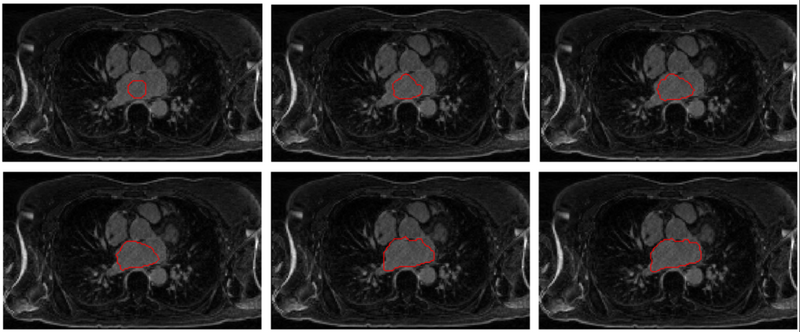

• Image-LASegWithMomentsPrior.png

Region-growing process driven by robust statistics and Zernike moments shape prior.